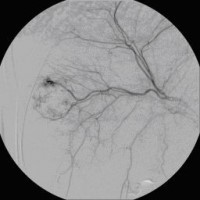

Superselektive transarterielle Chemoembolisation (TACE) mit Sondierung eines tumorversorgenden Gefäßes 1

(Bild 3 von 5)